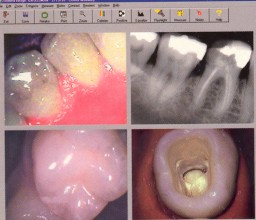

We are dealers for Sopro Imaging and can supply the popular PSPIX and Digora Optime Scanners fully integrated to the Shire Dental System.

Smart design, ergonomics and compact with a consistent image quality, PSPIX, the new Digital Imaging Plate System is designed to make intra oral imaging in the dental office easier and more efficient.

Four sizes of Imaging plates, thin and flexible with an active area optimized to 100%.

With PSPIX, the readout process of 4.3 sec. is completely automatic and a screen allows you to control the different steps of the process and to view your shot.

Fully Integrated to the Shire Dental System allowing images to be viewed on any woorkstation.

We are happy to link to any other type of digital x-ray, inter-oral camera and digital photographs.

We have developed sophisticated links to Image handling software such as the Schick Technologies CDR Dicom for Windows, Sopro, Kodak Trophy, Dexis, Owandy QuickVision & Gendex.